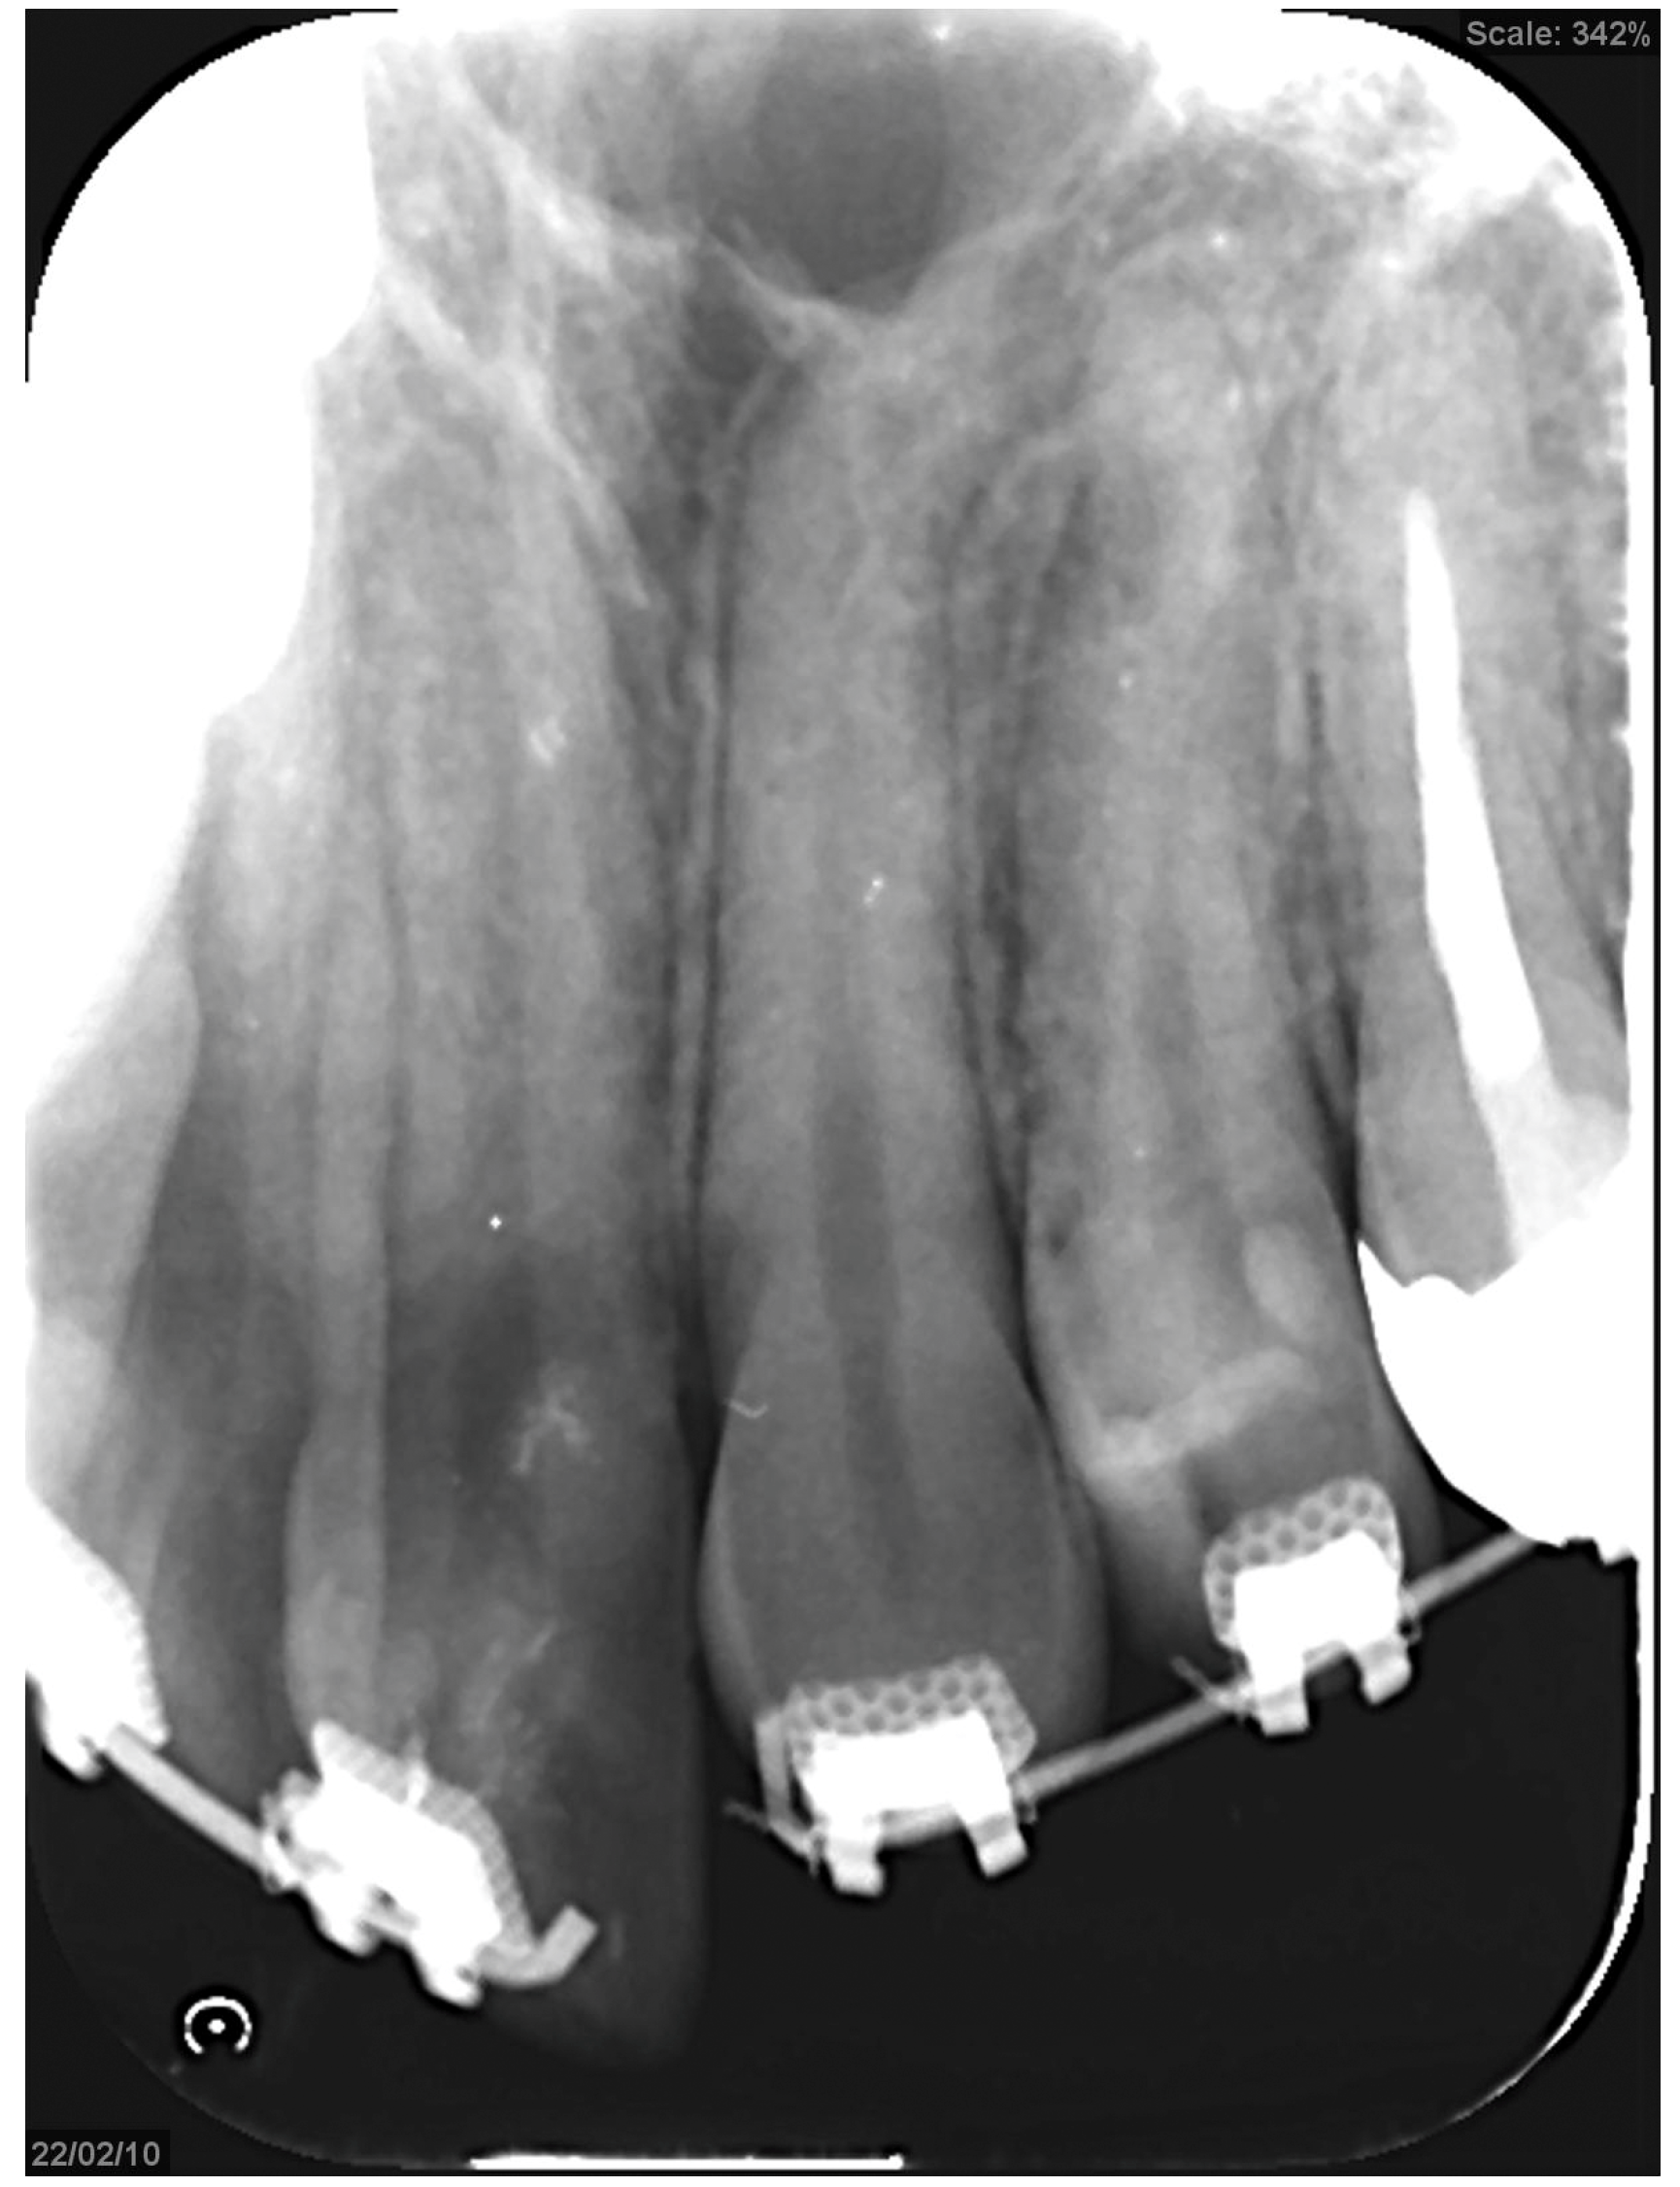

Figure 6.

An open coil creates a space between the upper right central incisor and canine to create a gap for the bone chisel.